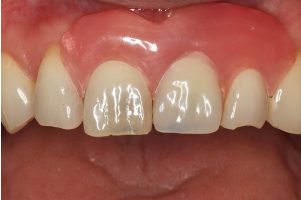

1歯欠損(インプラント1本)

治療前

治療後

歯根破折により、前歯を1本喪失しました。ブリッジ治療と迷われましたが、インプラント治療を選択され、両隣在歯を削らず修復することができました。